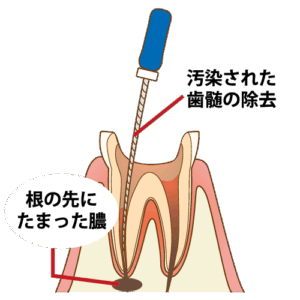

⏫①茶色くなっている部分が、虫歯で感染した神経の部屋です。この部分を数回に分けて綺麗に治療していきます。

⏫③音の鳴らない小さな器具を使い、溜まった膿をグリグリと綺麗に取り除いていきます。